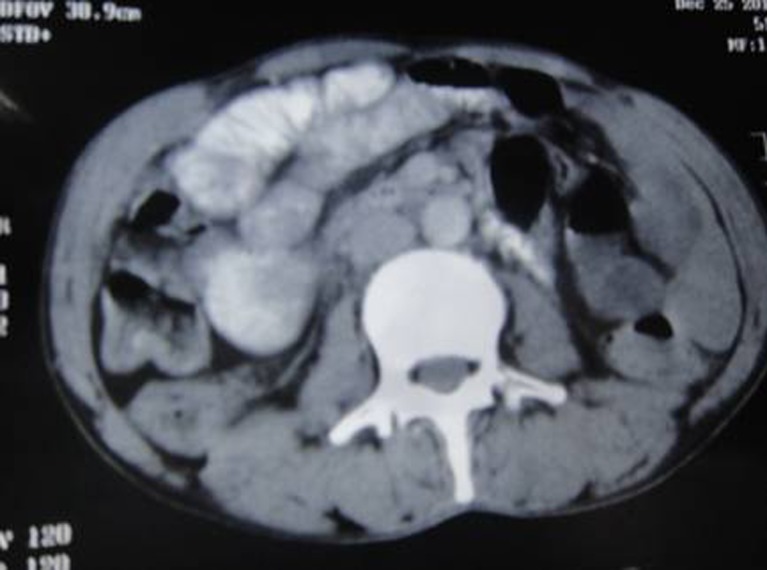

We report a case of a 55-year-old man who was admitted to the surgical emergency department with pain in abdomen, generalized distention, vomiting, and inability to pass flatus and feces. On clinical examination, he was anemic, dehydrated with PR 120/min, BP 90/70 mmHg, RR 30/min, and temperature 100°F. His abdomen was distended with a tender mass in the right iliac fossa along with increased bowel sounds. The patient gave previous history of a gradually progressing mass in the right iliac fossa, dull pain in the lower abdomen, low-grade fever, anorexia, and weight loss. For these problems he was kept on conservative treatment with partial response. Video colonoscopy done at that time revealed circumferential ulcero-nodular growth at the cecum. Multiple biopsies were taken which showed loose stroma infiltrated by tumor cells of small to medium size, round to oval in shape, having hyperchromatic nuclei with homogenous chromatin and scant cytoplasm. Later the patient was admitted and investigated in our unit. His investigation showed Hb 8 mg/dl, TLC 10,200 mm3, DLC P60, L35, E02, M02, B01, RBS 86 mg/dl, S. Na+ 136, S. Ka+ 4.3, S. Ca+2 4.49, S. urea 23 mg/dl, S. creatinine 0 .7, INR 1.04, and serum CEA 1.23 ng/ml. On CECT abdomen, findings were suggestive of diffuse thickening of the ascending colon and cecum with obliterated lumen and a nodular mass in the right iliac fossa (Figs. 1 and 2).

Fig. 1.

CECT abdomen showing cecal growth

Fig. 2.

CECT abdomen showing enlarged lymph nodes along with dilated bowel loops